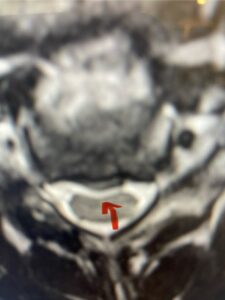

In this next case, this patient is a 47 year-old female who presents with intractable low back pain with severe pain, numbness, and weakness in the right lower extremity that had gotten progressively worse over a year. The patient had failed conservative management including physical therapy and epidurals. She was noted to have ⅘ weakness of plantar flexion. MRI demonstrated a large right L5-S1 disc herniation with severe compression of the descending right S1 nerve root (Fig 3). It was decided to perform a right L5-S1 hemilaminectomy for removal of the disc fragment and decompress the S1 nerve root. When you expose the disc, one must be certain to release any anterior adhesions to the nerve root in order to prevent a dural tear during retraction of the nerve root. It is also important to make sure during exposure and you finally encounter the dura after removing the ligamentum and fat, to make sure you are looking at the nerve root and not the main trunk of the thecal sac because if you don’t you can avulse or damage the nerve root if you retract the wrong structure.

Fig. 3a: Sagittal and axial T2-weighted lumbar MRI images demonstrating large right L5-S1 disc herniation (red arrows)

Fig. 3b